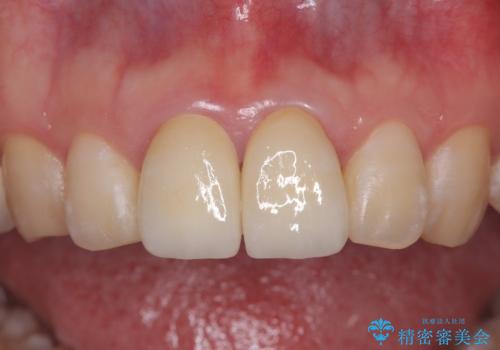

精密根管治療後、オールセラミッククラウンで治療を行いました。

治療後、違和感は無くなりました。

- 39.6万円(精密根管治療イニシャルケース11万円+ファイバーコア2.2万円+仮歯1.1万円×2+オールセラミッククラウンスタンダード12.1万円×2)費用は治療当時の料金となります

治療後、違和感が無くなり、被せ物で歯の長さが揃い見た目も改善されとてもご満足していただけました。